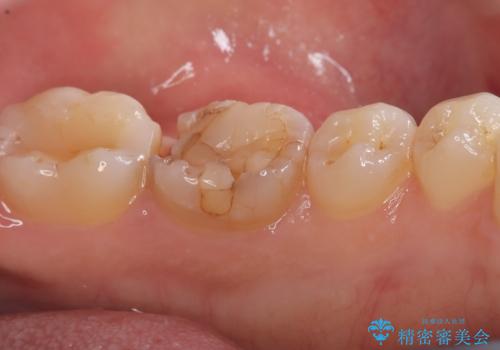

- 主訴:強く噛んだら歯がポロポロ欠けてきた。

左下6番目の歯の咬合面にプラスチックの材料が詰まっており、歯質がドーナツ状にしか残っていなかったため、歯質幅が比較的薄かった場所が欠けてしまったようでした。

頬舌的レジンインレーが入っており、歯質幅の薄かった且つ強く咬合していた遠心側歯質が欠けてしまっていました。また新しい窩洞のインレーを入れても、近心側歯質の破折のリスクは抱えたままになることから、クラウンでの修復をおすすめし審美性・適合性のよいセラミッククラウンでのやり替えとなりました。